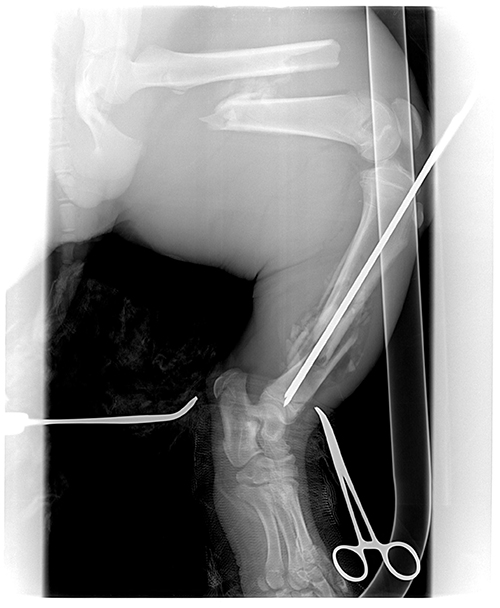

By day 14 our veterinarian felt he was strong enough to set his leg. Both large bones in his left hind leg were badly broken (see pictures above). The operation took almost five hours. She put rods through the center of the bones. It was a very big job, but everything went well.